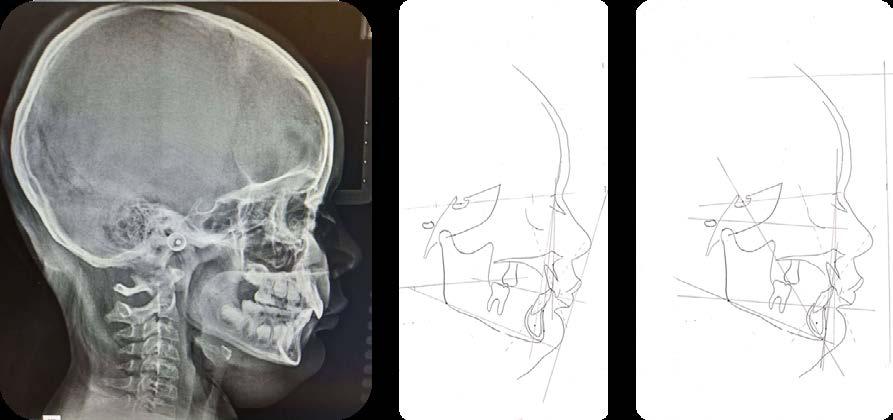

h. Realizar con las diferentes tablas de análisis cefalométricos, el análisis de proyección de crecimiento óseo maxilomandibular respecto a la edad del paciente y secuencia de erupción presente al momento del diagnóstico, es decir, si la secuencia de erupción está acorde

Figura 9.

o alterada, así como determinar la clase esqueletal del paciente y su tendencia en dirección, crecimiento y dimensiones hacia el cierre del crecimiento craneodentofacial (Figura 15).

Como podemos observar, tener una referencia del crecimiento y desarrollo craneodentofacial es básico para poder medir, verificar y diagnosticar correctamente la posición del canino, su trayecto, los tiempos biológicos de crecimiento óseo y así poder tener más referencia de la proyección y posibles causas que generan interferencias y que impliquen una inclusión canina.30

propósito de ubicar al canino con posibilidades de incluirse, en su trayectoria de erupción, está el desarrollado por el Dr. Ricketts, 5 que además de ser una herramienta para planificación de un tratamiento interceptivo ortodóntico adecuado, permite visualizar y el trayecto de formación y erupción del canino, esto es, utilizando radiografías laterales de cráneo, aplicando la técnica de superposición (Figura 23).

Este método es el más utilizado en la actualidad7 y se complementa con un área de estudio que detecta cambios dimensionales y de dirección de crecimiento, tanto en el maxilar como en la mandíbula.6 El apoyo de este análisis, es el punto de partida para tomar acciones interceptivas, en beneficio de obtener los espacios suficientes para el acomodo de caninos y de ese modo evitar su inclusión.